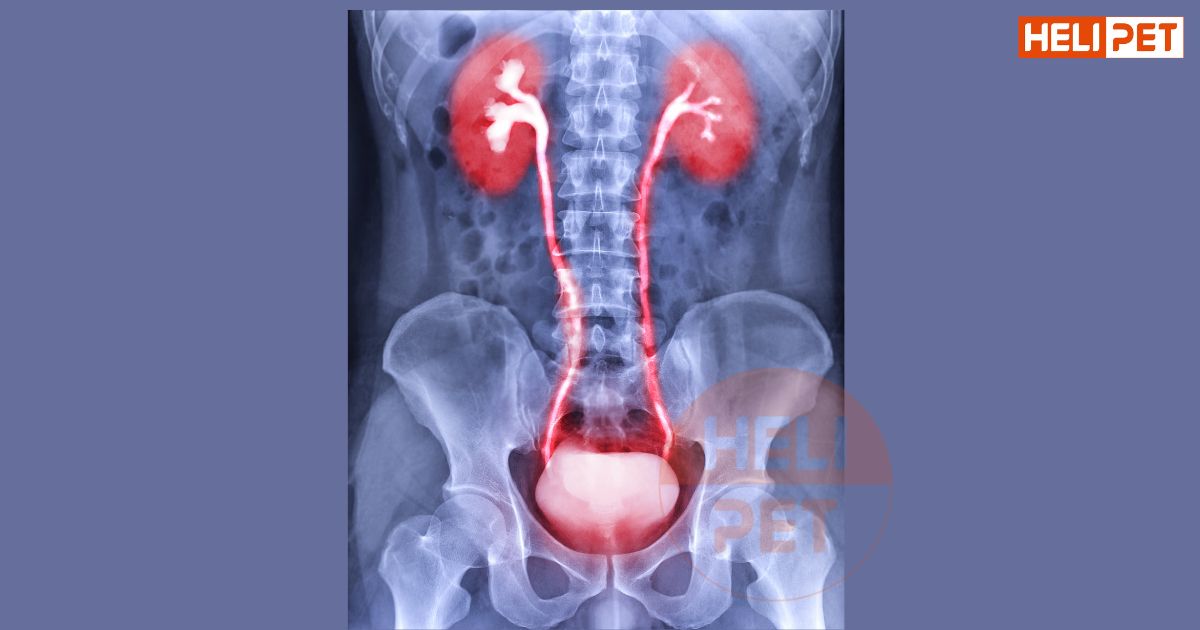

1. Viêm tiết niệu ở mèo là bệnh gì?

Bệnh đường tiết niệu dưới ở mèo (FLUTD) là thuật ngữ chung để chỉ một loạt các triệu chứng lâm sàng, do niệu đạo bị tắc nghẽn hoặc bàng quang không thể thải nước tiểu ra ngoài đúng cách. Những tình trạng này có thể trở nên nghiêm trọng, thậm chí đe dọa đến tính mạng nếu không được điều trị kịp thời.

3. Cách chẩn đoán mèo bị viêm tiết niệu

Bác sĩ thú y sẽ thăm khám và lấy mẫu nước tiểu của mèo để kiểm tra, trong một số trường hợp có thể cần xét nghiệm máu. Sau khi xác định nhiễm trùng đường tiết niệu, bác sĩ sẽ tư vấn phương pháp điều trị phù hợp nhất cho mèo của bạn.